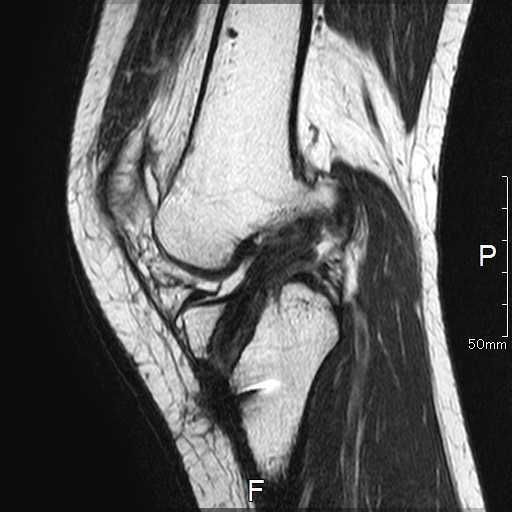

MRI所見

| 手術前 | 手術後 |

![]() |

| ACLの緊張および連続性は消失している | 再建靭帯の成熟をみとめる |